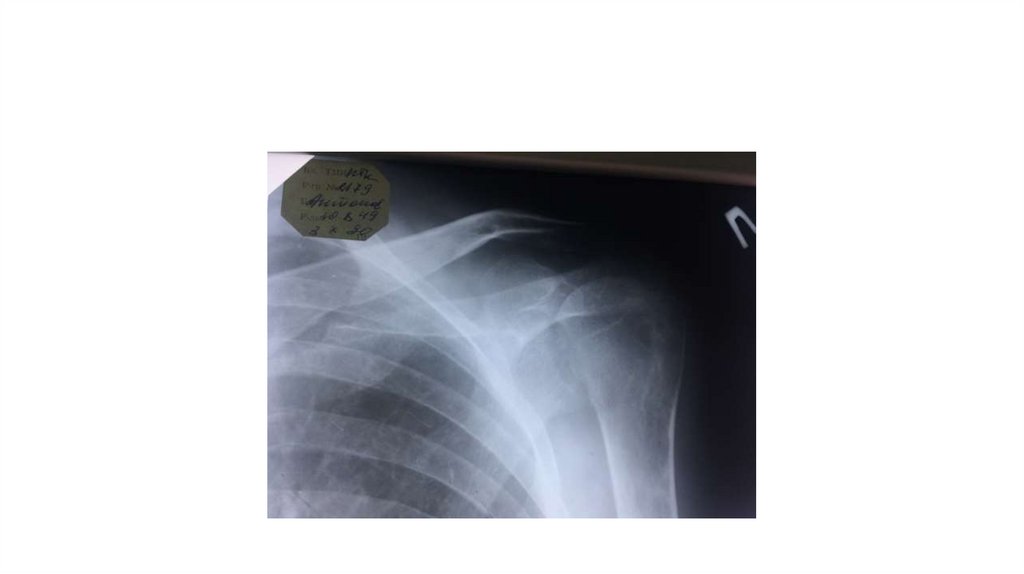

Воспалительные заболевания опорнодвигательного аппарата

заболевания опорнодвигательного аппарата»